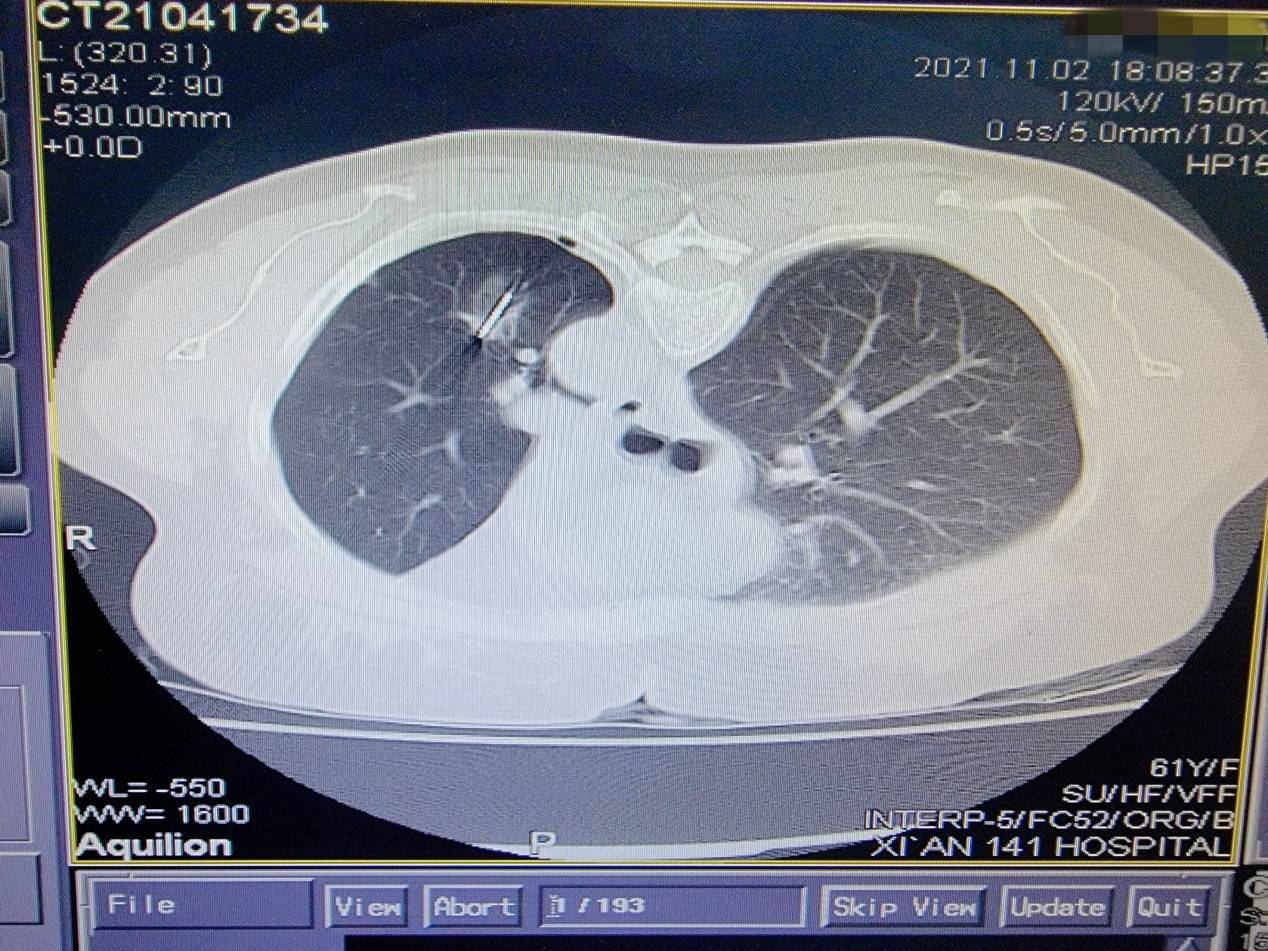

来自商洛市61岁的刘女士2年余前因左肺癌于西安交大一附院东院区行“胸腔镜左肺上叶癌根治术” , 10天前复查行胸部CT发现左肺下叶结节 , 进一步行PET/CT示:左肺下叶结节 , 核素摄取异常 , 考虑转移癌 。 患者慕名来到付军科主任领衔的东院区胸外科就诊 , 付军科主任仔细查阅患者既往病历资料 , 临床诊断为转移结节 , 由于2年前已经实施肺叶切除术 , 经多学科讨论后决定给患者行肺结节微波消融术 。

11月2日下午 , 在医学影像科协助下 , 东院区胸外科团队成功开展了东院首例肺结节微波消融术 , 整个治疗过程非常顺利 , 患者无明显不适及并发症发生 , 术后复查胸部CT显示微波消融范围理想 , 病灶位于消融靶心 。